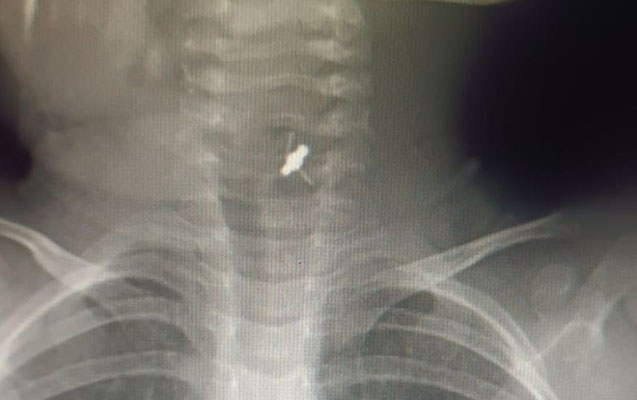

Həkim bildirib ki, azyaşlı tibb müəssisəsinə tənəffüs çatışmazlığı və boğulma şikayətləri ilə gətirilib:

“Aparılan müayinələr əsasında xəstənin yad cisim udduğu məlum olub. Xəstəyə bronxoskopiya icra edilərək baş bronx mənfəzindən yad cisim - saç sancağı xaric edilib”.